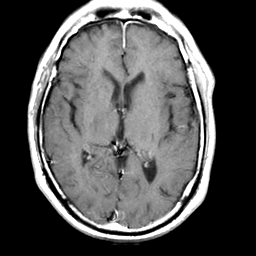

Meningioma, MR Study #2 -- Slice #10

[Home][Help][Clinical] Slice 10